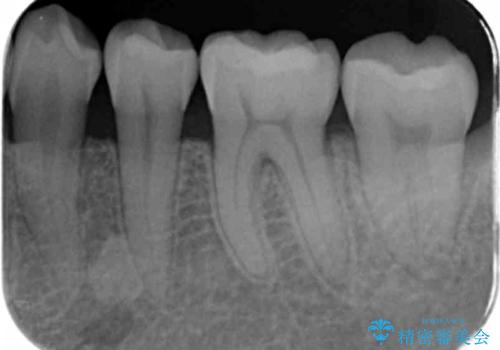

- 奥歯の樹脂の色が気になるとのことで来院されました。

変色しない材料での治療をご希望されたためセラミックインレーでの治療をしていくこととなりました。

継ぎ接ぎになった樹脂の詰め物から一塊のセラミックインレーに置き換えることで着色や二次う蝕のリスクを抑えます。